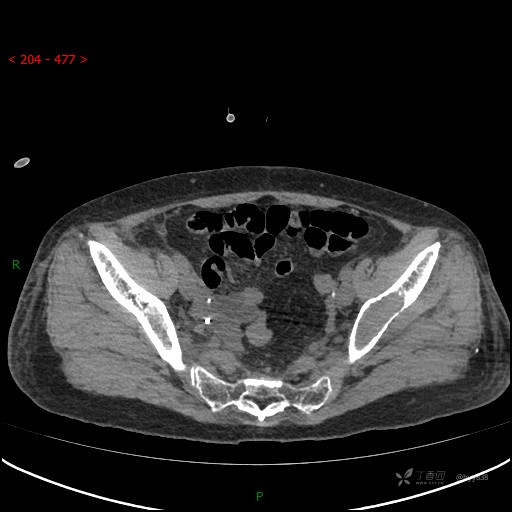

CT平扫